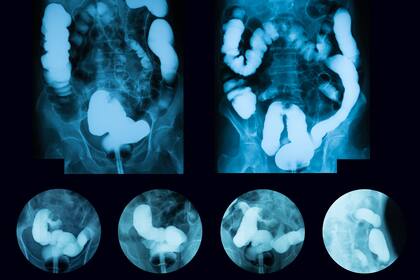

"El cáncer colorrectal es la aparición dentro del colon o del recto de un crecimiento desordenado e injustificado de las células de la mucosa de estos órganos, produciéndose un tumor que puede llegar a diseminarse en todo el organismo a través de la sangre y de los vasos linfáticos", explica el especialista.

También puede producir obstrucción del propio intestino grueso haciendo que el paciente tenga que buscar ayuda urgente, y en muchas ocasiones ser intervenido quirúrgicamente, según advierte el oncólogo.